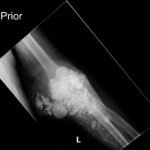

Calcinosis cutis is a condition in which calcium-phosphate salt deposits are formed in cutaneous and subcutaneous tissue. A subtype, metastatic calcinosis cutis, can occur in patients with disorders that cause hypercalcemia or hyperphosphatemia such as end stage renal disease. We present a case of a 67-year-old man with end-stage renal disease (ESRD) on dialysis who presented to the emergency department with a draining left elbow wound. On exam, he had irregular, firm nodules palpable in the subcutaneous tissue of both large and small joints. The presence of calcinosis cutis on imaging and lack of other findings suggesting infection led to outpatient wound care treatment. Recognizing the appearance of calcinosis cutis on imaging and conditions that present with calcinosis cutis is important for the emergency physician.